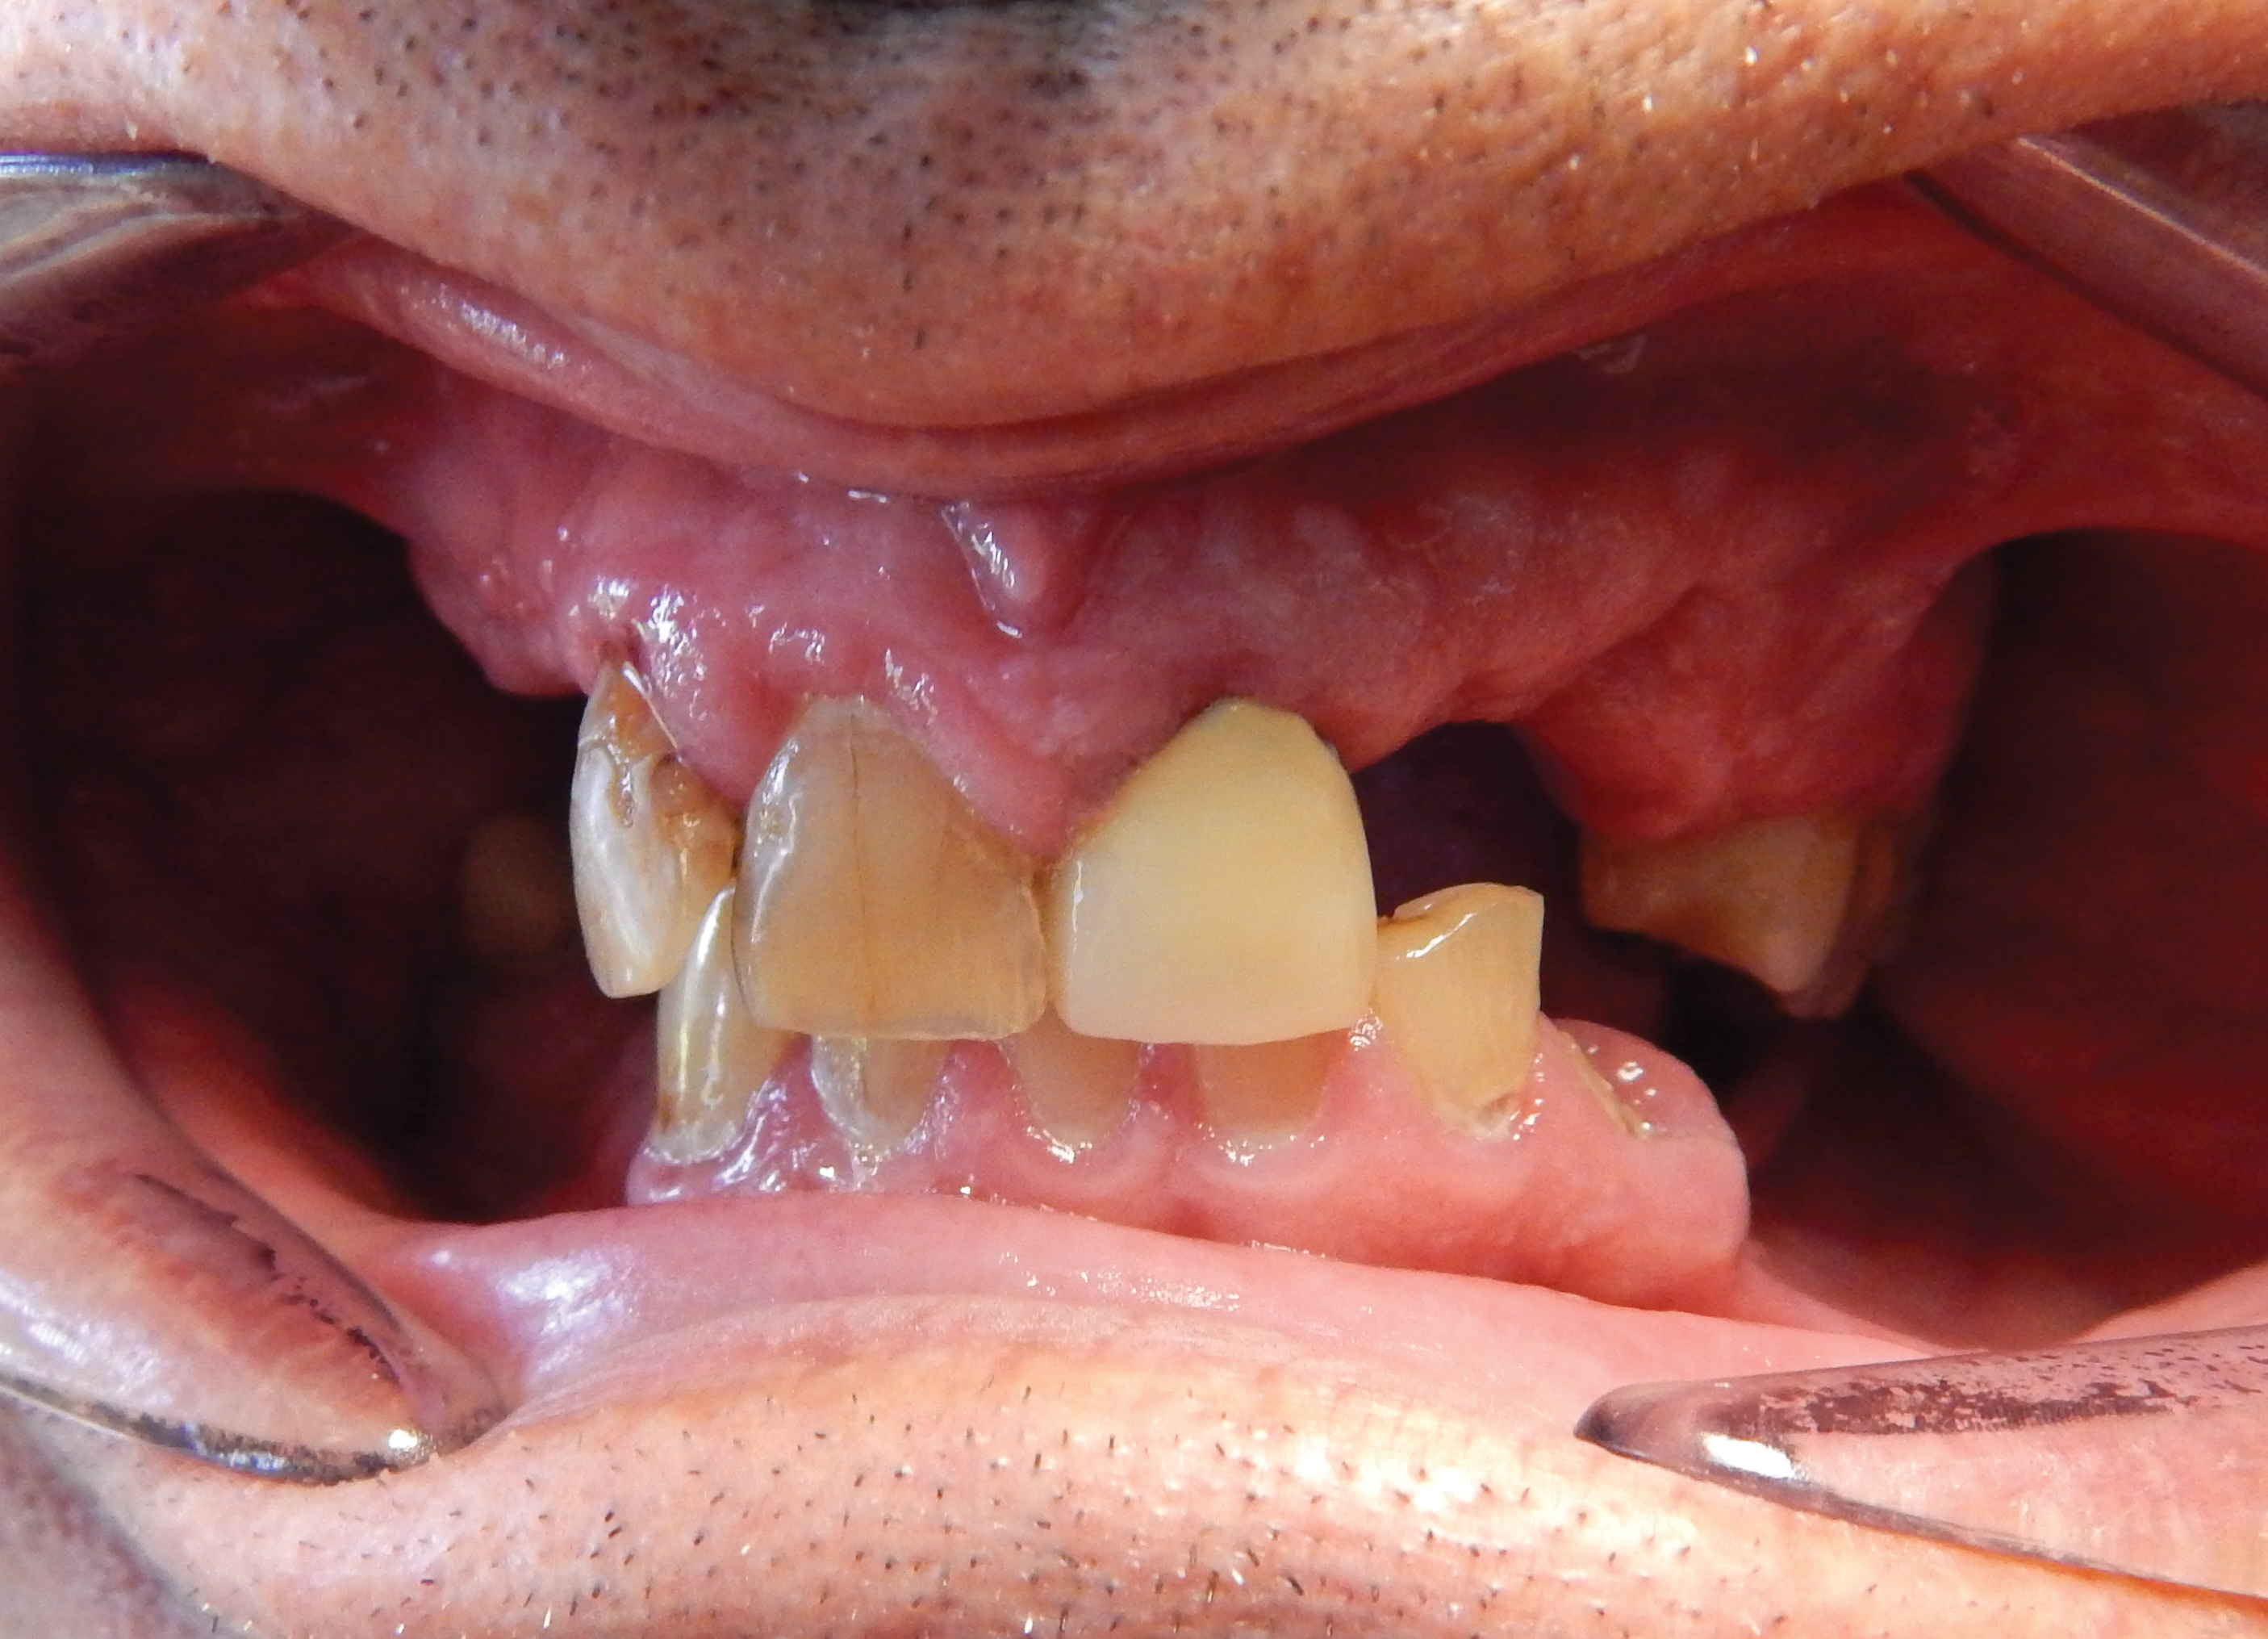

Full Protocol Transition Through Extractions And Acrylic Based Immediate Dentures To Metal Based Definitive Dentures Finlay Sutton. Thirty years old ch.107 : I feel lucky & appreciative to be a part of a great community of fellow denture wearers. I can never have my permanent teeth back and i am really dealing with the loss of my teeth. For the 4,764th time, age perception is relative. Wow, your child is 3! I am a 36 year old woman who has had to have all of my upper teeth removed and i now have a upper denture. At 36, i was in the best physical condition of my life. Thirty years old ch.100 : I know i now have the smile that i've been wanting for years but at what cost? Having these items helps me. I feel scared and alone. Sun, 27 dec 2020 11:54:58 gmt. Can't believe it's already been 8 weeks since i got my dentures. People younger than age xx will think people of now, at 69, i laugh when i hear someone calling a guy, or woman for that matter, old at 36. Reservation at the presidential suite.